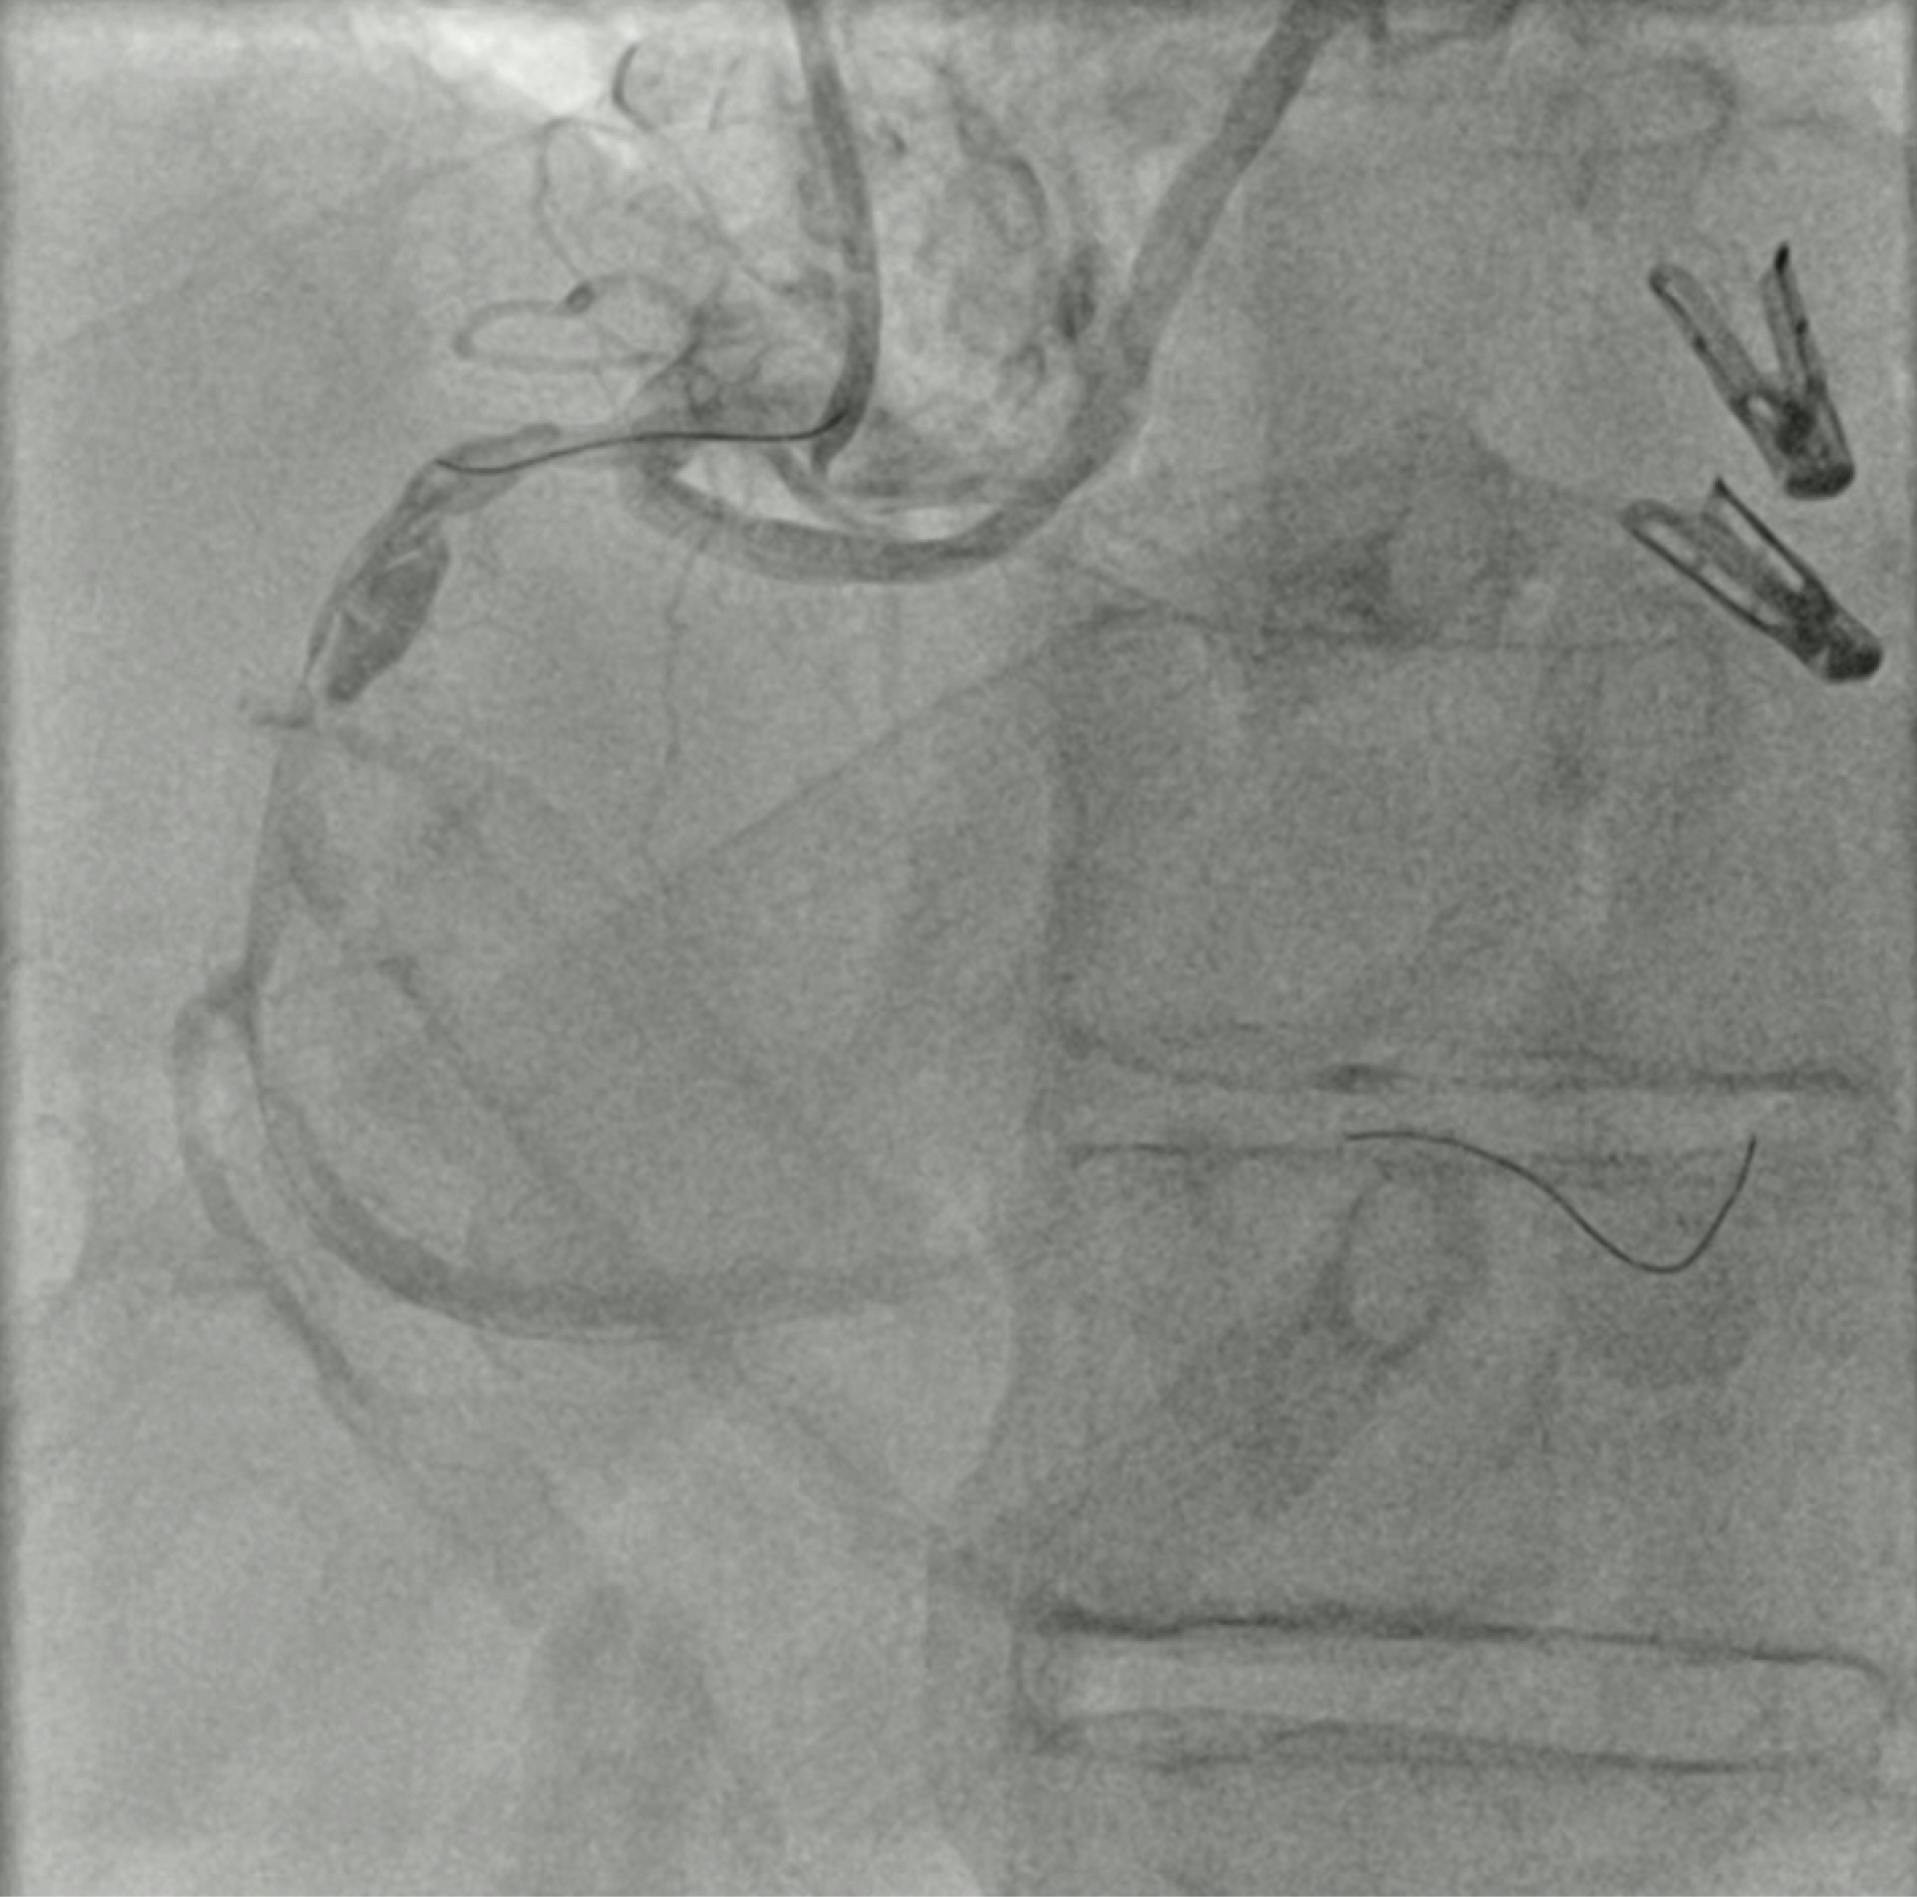

In the dominant RCA, a proximal aneurysm was present, associated with an ulcerated plaque and a severe stenosis in the distal part of the aneurysm. The aneurysmatic RCA was also characterized by a grade 4 thrombus (Figure 1).

Figure 1. Preprocedural angiogram of the left PA.